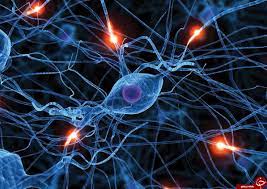

قیمت: 96٬000 تومان - دسته بندی فایل: پاورپوینتپاورپوینت فیزیولوژی اعصاب

فروش ویژه پاورپوینت حرفه ای فیزیولوژی اعصاب / تعداد اسلاید: 231 اسلاید

قیمت: 52٬000 تومان - دسته بندی فایل: پاورپوینتپاورپوینت فیزیولوژی درد

فروش ویژه پاورپوینت حرفه ای فیزیولوژی درد / تعداد اسلاید: 37 اسلاید